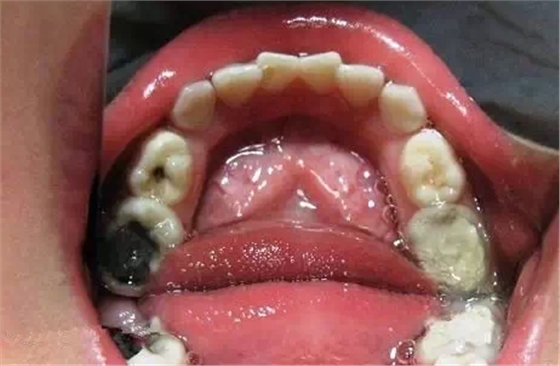

乳牙急性根尖周炎的應(yīng)急處理,首先應(yīng)建立髓腔引流,用快速鋒利的渦輪機(jī)牙鉆開髓,開放髓腔,使炎性滲出物或膿液通過根管引流。 (福建醫(yī)大口腔醫(yī)院 高生輝老師的圖片)

已形成粘膜下膿腫的還需在口腔內(nèi)的腫脹部位做局部切開排膿,而腫脹嚴(yán)重者,則需用碘仿紗條進(jìn)行引流。(醫(yī)大口腔醫(yī)院 高生輝老師圖片)

(以上圖片引用自福建醫(yī)大附屬口腔醫(yī)院兒童科 高生輝老師的課件,非常感謝!)